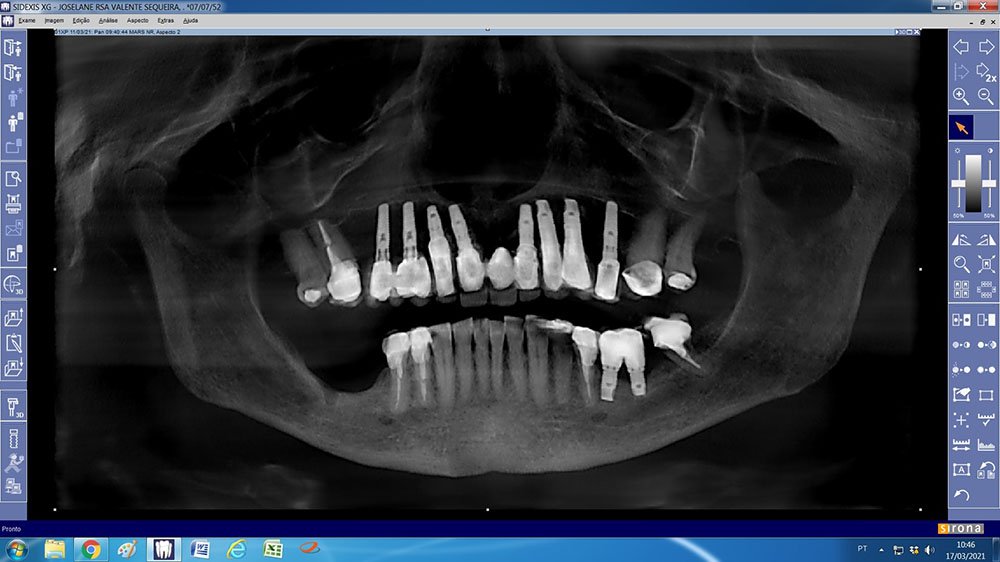

Neste relato, apresentamos um caso clínico onde necessitamos realizar um aumento ósseo vertical e horizontal, no qual optamos por utilizar um biomaterial composto de colágeno tipo 1 e hidroxiapatita bovina (Extra Graft), e uma membrana de PTFE denso com reforço de Titânio (Cytoplast TI-250) para realizar a regeneração óssea guiada na região posterior da mandíbula.